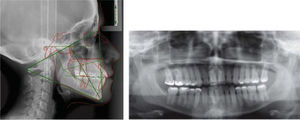

In the cephalometric analysis she was a skeletal class III, mesocephalic, with a concave profile, neutral growth and lower lip protrusion (Figure 1). In the panoramic radiograph she presented 28 erupted permanent teeth, loss of alveolar crests and a root-crown ratio of 3:1 (Figure 2).

Facially, she presents a concave profile, mesofacial pattern, decreased upper facial third, asymmetry, neutral smile, lip competence and a slightly everted lower lip. Upon clinical examination and intraoral analysis, it was observed bilateral molar class III, a canine class III, a 3mm overbite, -2mm overjet, moderate lower dental crowding, dental midline deviation, ovoid upper and lower arch form, unilateral anterior and posterior crossbite and controlled generalized chronic periodontitis (Figures 3 at 5).